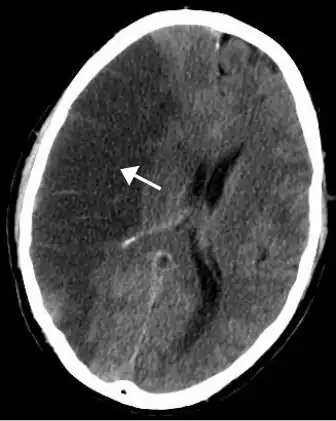

CT scan of an intraparenchymal bleed (bottom arrow) with surrounding edema (top arrow)

There are two main types of hemorrhagic stroke:[30][31]

The above two main types of hemorrhagic stroke are also two different forms of intracranial hemorrhage, which is the accumulation of blood anywhere within the cranial vault; but the other forms of intracranial hemorrhage, such as epidural hematoma (bleeding between the skull and the dura mater, which is the thick outermost layer of the meninges that surround the brain) and subdural hematoma (bleeding in the subdural space), are not considered "hemorrhagic stroke".[32]

Hemorrhagic stroke may occur on the background of alterations to the blood vessels in the brain, such as cerebral amyloid angiopathy, cerebral arteriovenous malformation and an intracranial aneurysm, which can cause intraparenchymal or subarachnoid hemorrhage.[33]

Intracerebral hemorrhage

It generally occurs in small arteries or arterioles and is commonly due to hypertension,[58] intracranial vascular malformations (including cavernous angiomas or arteriovenous malformations), cerebral amyloid angiopathy, or infarcts into which secondary hemorrhage has occurred.[2] Other potential causes are trauma, bleeding disorders, amyloid angiopathy, illicit drug use (e.g., amphetamines or cocaine). The hematoma enlarges until pressure from surrounding tissue limits its growth, or until it decompresses by emptying into the ventricular system, CSF or the pial surface. A third of intracerebral bleed is into the brain's ventricles. ICH has a mortality rate of 44 percent after 30 days, higher than ischemic stroke or subarachnoid hemorrhage (which technically may also be classified as a type of stroke[2]).